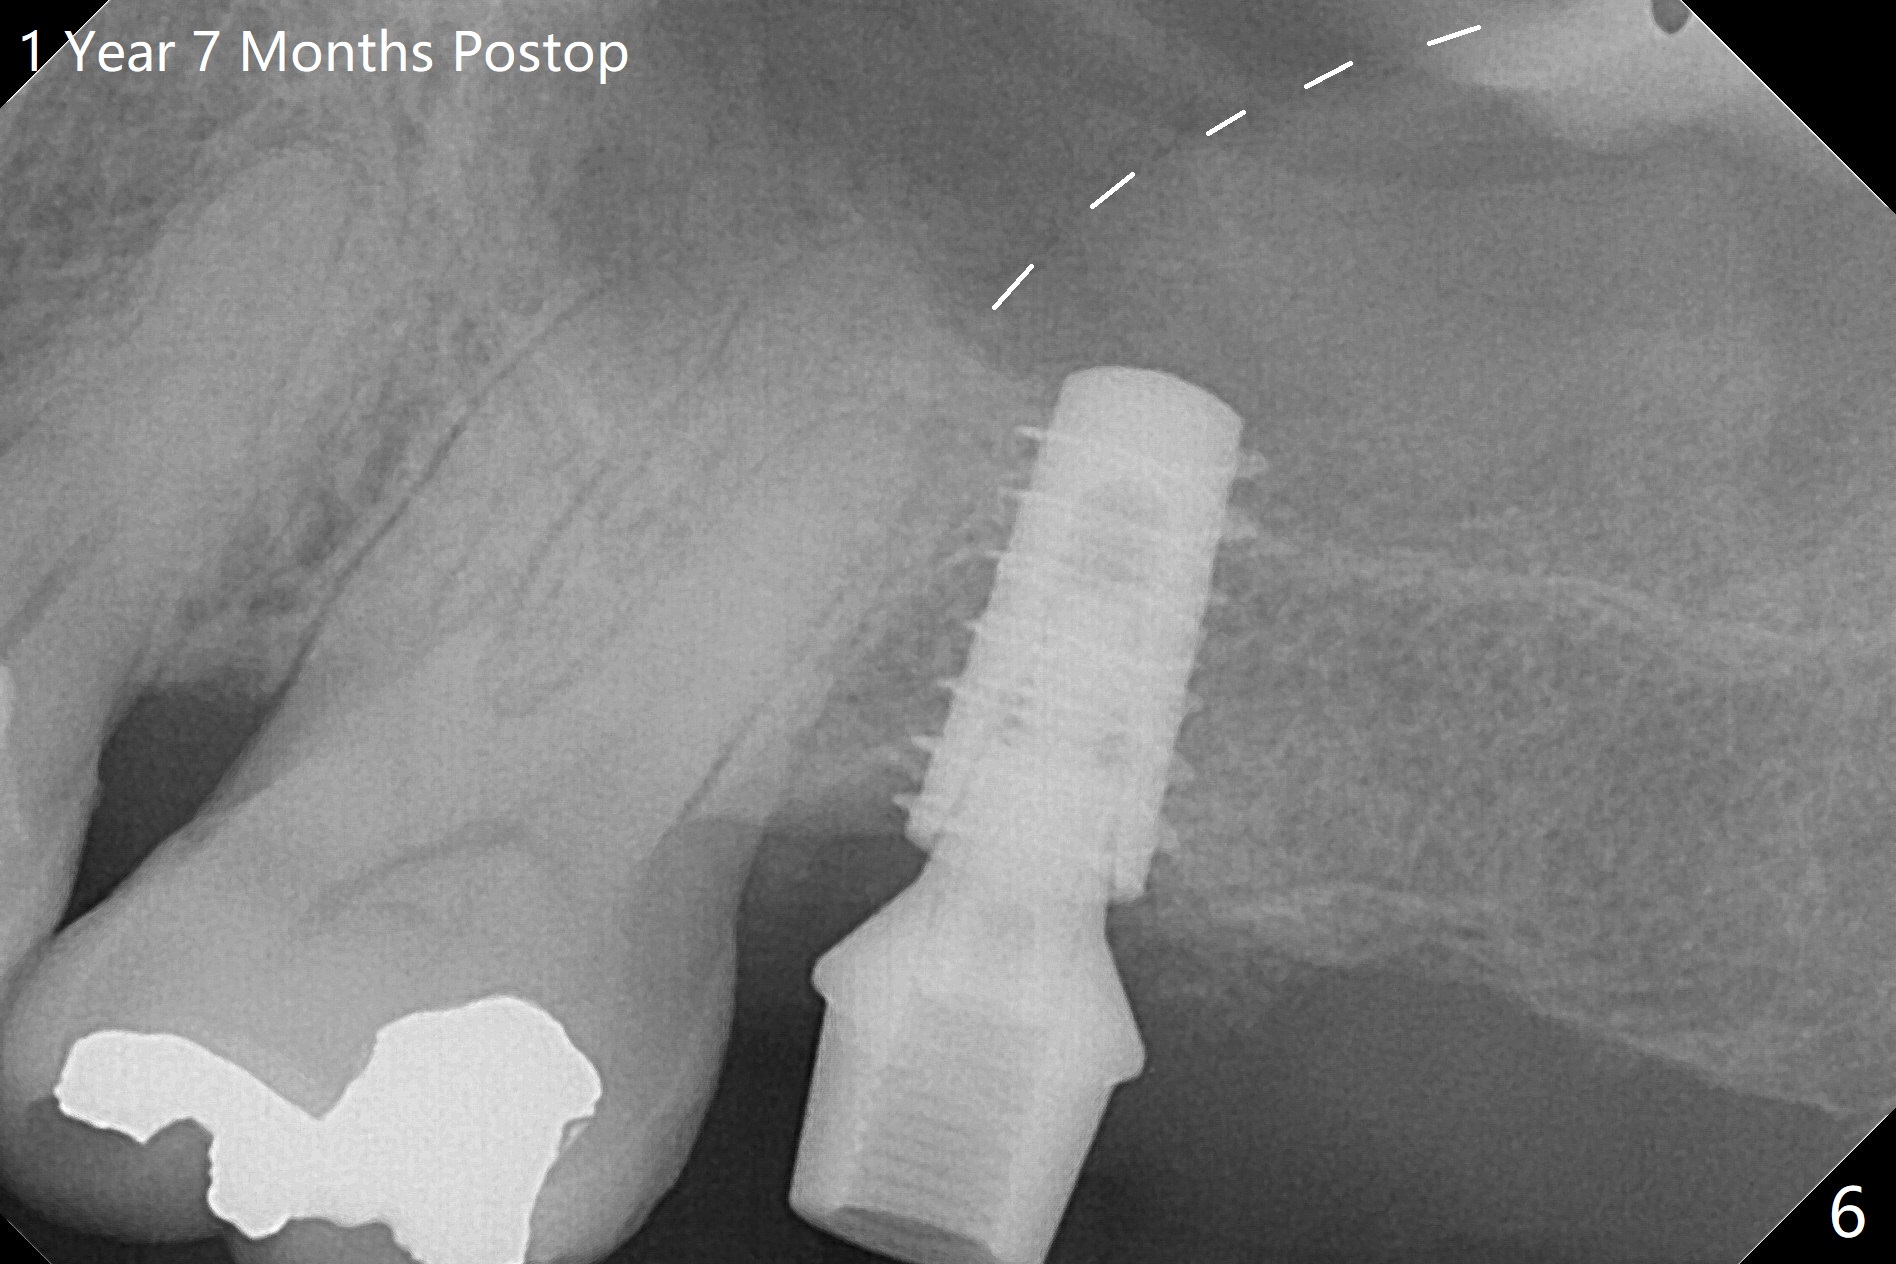

Designed osteotomy depth is 7.3 mm IS drill with 4 rings at #15. In fact osteotomy is created using 2.2 mm drill with 2 rings (sinus membrane barely visible from the osteotomy) and 3-4 mm ones with 3 rings. With an amalgam carrier of bone graft, sinus lift is initiated with 4x9 mm dummy implant (Fig.1). After loaded with totally 5 amalgam carriers of bone graft repeatedly with the 4x9 mm dummy implant, a 5x9 mm implant is placed with ~ 25 Ncm. After insertion of a 6x4(2) mm abutment, sticky bone cut into pieces (Fig.2) is inserted to peri implant space (Fig.3 *), followed by PRF and an immediate provisional. The latter dislodges 7 days postop; the socket starts to heal (Fig.4); the bone graft seems to be fixed in place. The provisional is reseated (no cement, Fig.5) without fear of its dislodgement again. The patient returns for cleaning 1 year 7 months postop (Fig.6,7). The socket heals, while the abutment is incompletely seated (Fig.7 <). Percussion at #18 disappears post RCT, whereas periapical radiolucency appears post RCT (compare Fig.8,9). When the 6x4(2) mm incompletely seated abutment is removed, the implant well is dirty. The smaller abutment with longer cuff is seated fully (Fig.10).